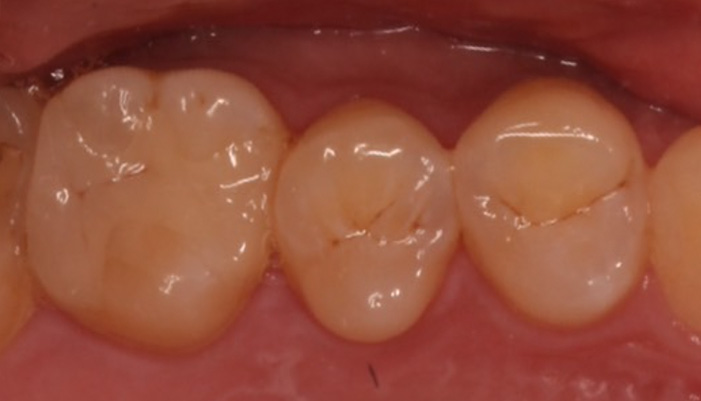

治療中

拡大視野下でむし歯の感染部位を丁寧に確認しながら正確に除去し、歯髄の状態を評価しました。その結果、神経を残せる可能性があると判断し、MTAを用いた歯髄温存療法を選択しました。神経を残すことは、歯の寿命を守ることにもつながります。

| 主訴 | 甘いものや冷たいものがしみる |

|---|---|

| 治療期間 | 1〜3回 |

| 治療費 | ¥33,000 |

| 治療内容 | 深い虫歯に対して歯髄を保護する処置を行い、神経を残す治療を行いました。 |

| 治療のリスク | 虫歯の進行度によっては将来的に神経の治療が必要になる場合があります。 |